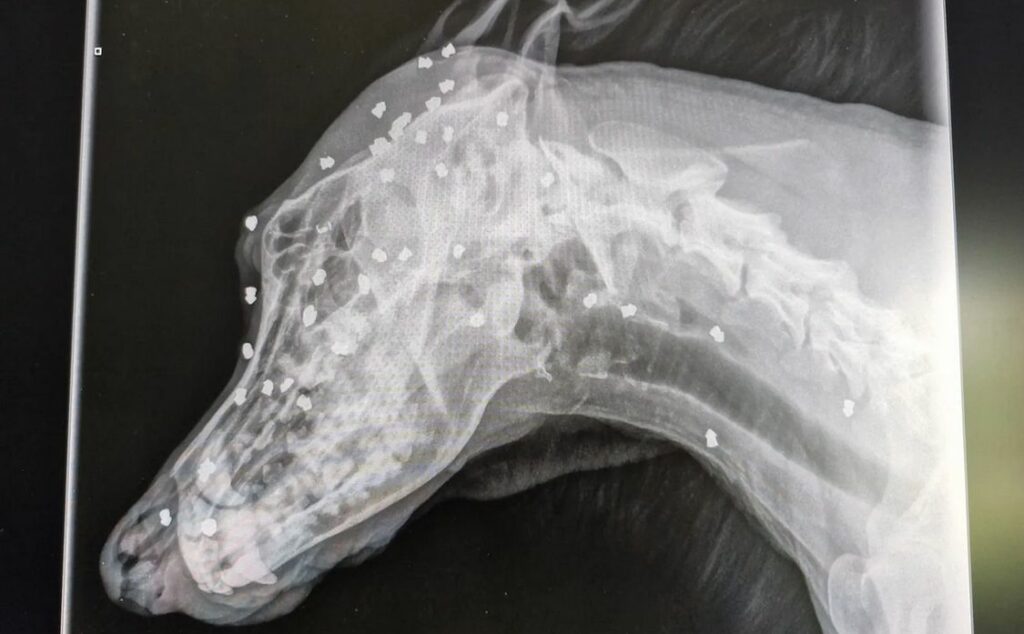

Los veterinarios confirmaron que el animal sobrevivió a más de 40 disparos de rifle de aire comprimido. La historia se conoció cuando el refugio de animales de Bautzen difundió radiografías del perro, que más tarde fue bautizado con el nombre de Keks.

Las radiografías revelaron un panorama escalofriante: 42 proyectiles en la cabeza y varios más en otras partes del cuerpo. Según el refugio, el ataque se produjo durante un período prolongado, con el uso de un rifle de aire comprimido. La hipótesis más firme sostiene que el propio dueño del perro fue quien realizó los disparos.

Los especialistas que atendieron a Keks indicaron que algunos de los proyectiles no podrán retirarse nunca. Están incrustados en huesos o muy cerca de vasos sanguíneos vitales, lo que hace imposible la cirugía. A pesar de ello, el animal logró soportar varias operaciones para extraer las balas más peligrosas.